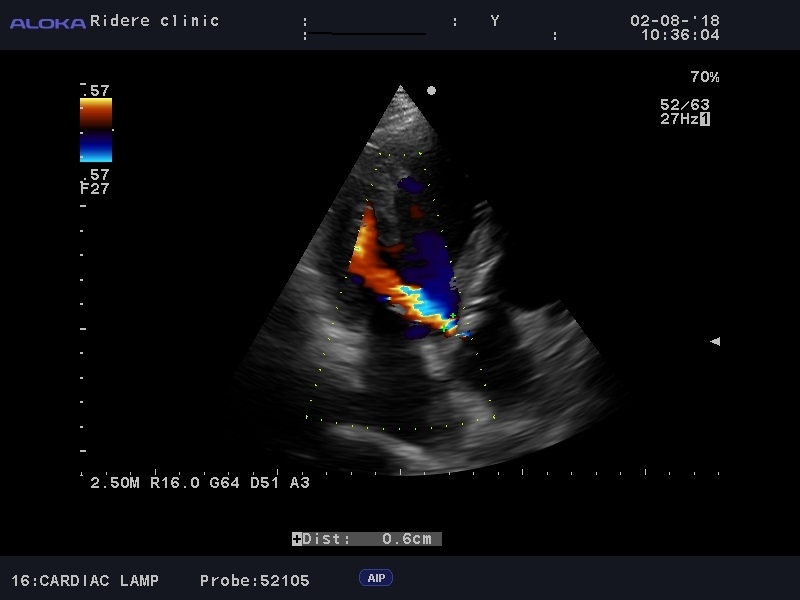

Патология митрального клапана, выраженная недостаточность МК с расширением левого предсердия.

Пациентка 70 лет, впервые обратилась с жалобами на одышку, при исследованиия выявлен порок митрального клапна, планируется замена митральго клапана.